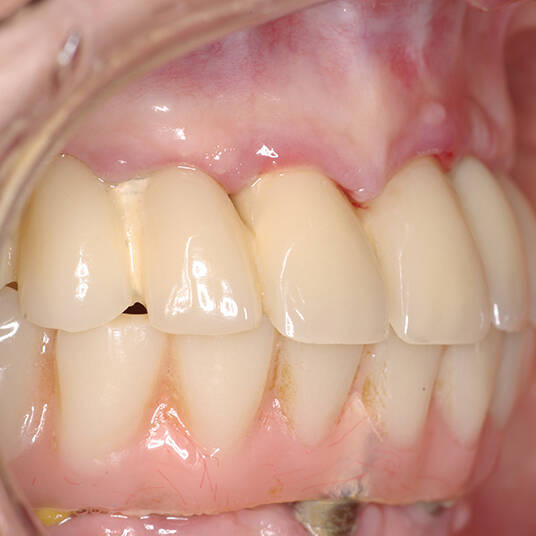

A Carga Imediata é uma técnica odontológica avançada que permite a colocação de uma prótese dentária fixa logo após a cirurgia de instalação dos implantes ou em poucos dias. Isso elimina a espera tradicional de meses para a integração completa do implante ao osso, oferecendo uma solução rápida e segura para restaurar dentes perdidos.

- Conforto e Estética: A prótese provisória é funcional e visualmente semelhante aos dentes naturais.

- Melhora da autoestima: O impacto positivo de um sorriso completo é imediato, melhorando a qualidade de vida.